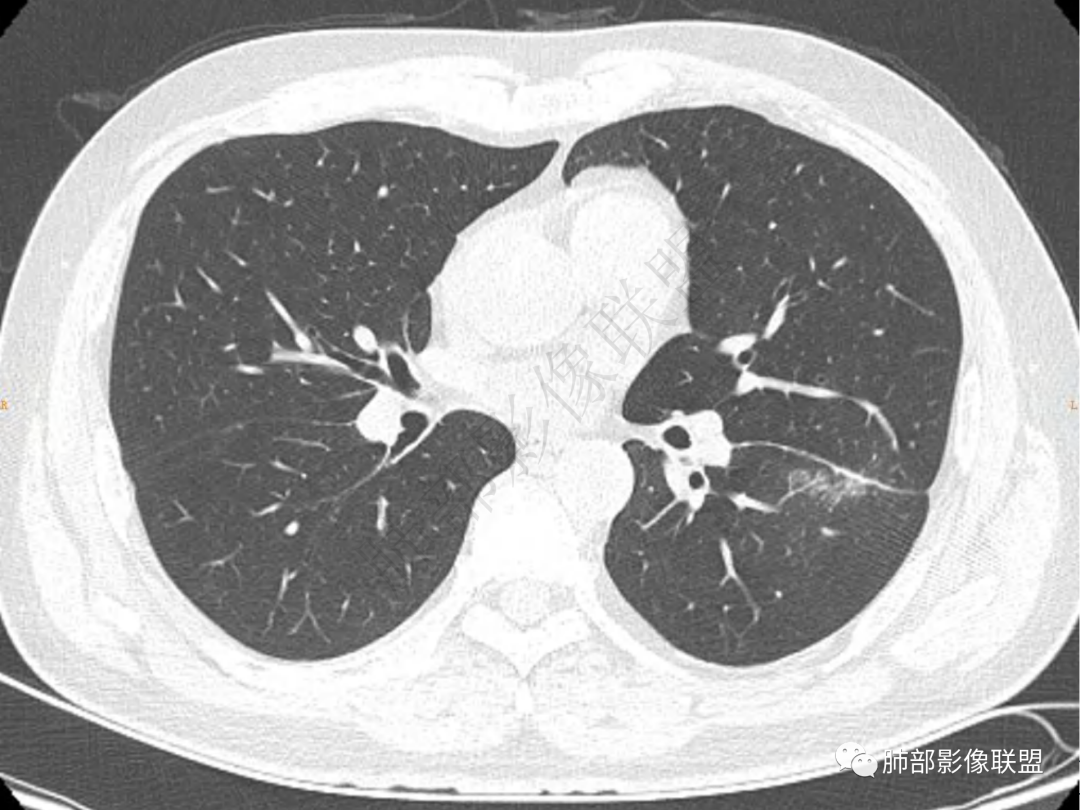

1.中年男性,咳嗽咳痰20余天,间断咯血2周

2.左肺下叶团片影,跨背段及内前基底段,实性部分类椭圆形,密度不甚均匀,可见毛刺及棘状突起,未见典型分叶及胸膜凹陷。病灶上下缘可见相应肺段支气管旁进侧出,管壁轻度增厚,未见狭窄阻塞。

3.周边较大范围磨玻璃影,边界相当模糊,小叶增厚明显。注意叶裂另一侧、左肺舌段亦可见磨玻璃影及增厚的小叶间隔。未见明确卫星病灶。

4.实性部分不均匀环形强化并显示一小范围低密度坏死区或空洞。较之肺窗,整体纵隔窗范围较小,提示病灶并不十分密实。抑或为不同时段图像。

5.双肺门及纵隔未见增大淋巴结。未见胸腔积液。